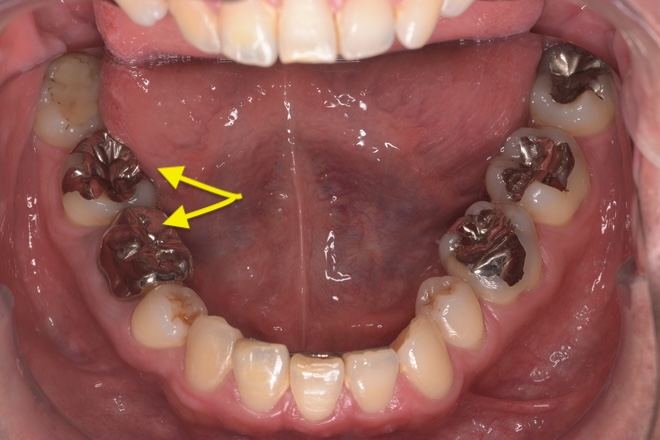

Case02下顎左右6番インプラント(マウスピース矯正を併用)

| 治療期間 | 6ヶ月 |

|---|---|

| 治療費 | インプラント2本1,100,000円 |

| 年齢・性別 | 20代女性 |

| リスクと副作用 | 腫れ、痛み、感染、神経損傷、将来的な脱落 |

| 備考 | 20代女性です。インプラント希望で来院されました。 他院でインプラントを入れるスペースがなく両方の歯を削る必要があると言われ、抵抗があるとのことでセカンドオピニオンで当院に来院されました。 赤坂さくら歯科クリニックオリジナルのインハウスアイライナーのサクライナー矯正で、隙間を閉じた上で一切削らずにインプラントを行いました。 患者様は隙間にものが挟まるストレスからも解放され、とても喜んでらっしゃいました。使用したインプラントはノーベルバイオケア社のインプラントになります。 大臼歯であっても細いインプラントを隙間を矯正などで調整しながら入れることが可能です。 |